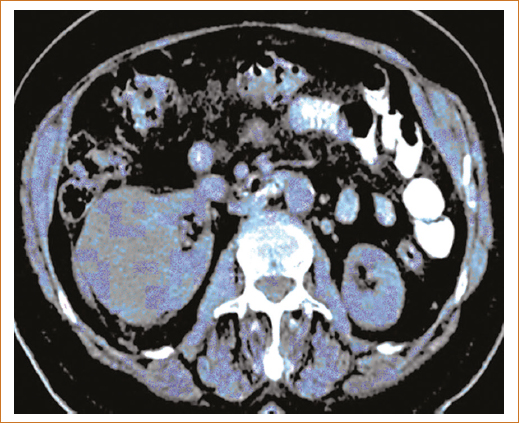

Es común encontrar quistes renales en el estudio de la función renal a los cuales no debe restarse importancia, ya que las masas renales quísticas se relacionan con incremento del riesgo de cáncer renal. Estas alteraciones aparentemente benignas tienen el potencial de complicarse desarrollando sangrado, dolor, infección y cáncer, este último se habrá que sospechar ante cambios de imagen en el control tomográfico (Fig. 1). Los quistes se clasifican en cinco categorías en función del aspecto tomográfico. La Clasificación de Bosniak ha correlacionado la morfología de las lesiones con el riesgo de malignidad, y, a su vez, establece recomendaciones terapéuticas (Tabla 2). La figura 1 muestra un quiste renal de grandes dimensiones con imágenes de alta densidad en su interior que obligan a descartan cáncer renal.

Figura 1. Corte tomográfico abdominal que muestra quiste degenerado.